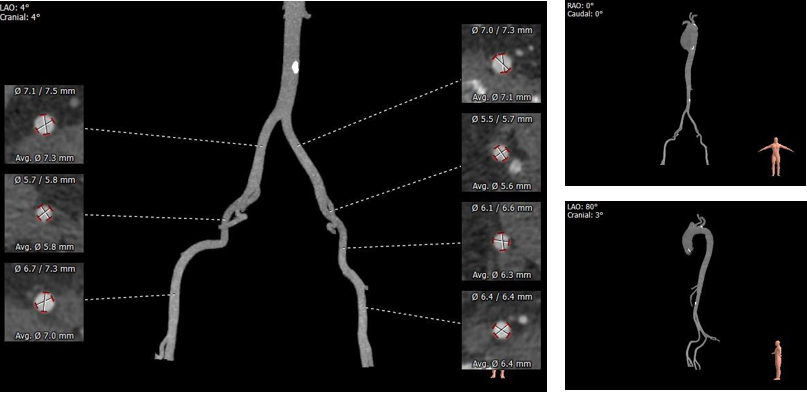

术前CT评估:

1.Type0型二叶式主动脉瓣,轻度钙化,钙化主要沿左冠窦瓣叶外侧边缘分布,瓣叶增厚,左冠窦瓣叶根部纤维赘生。

2.左右冠开口高度尚可,切线位右窦瓣叶长度>瓣叶附着缘到冠脉开口距离。

3.瓦氏窦内径,窦管交界、升主动脉内径可。

4.流出道呈收口状,收缩期小左室,心肌增厚,主动脉弓距及弓部夹角可。

5.双侧股髂动脉未见明显迂曲,髂外动脉管腔内径偏细,整体血管条件良好。

主动脉根部评估:

根部概览

瓣上评估:

外周血管及主动脉弓解剖: